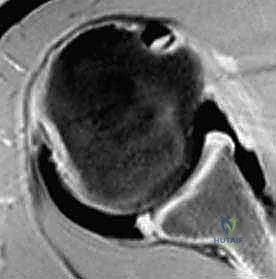

2. التصوير بالرنين المغناطيسي (MRI) أو الرنين مع الصبغة الملونة (MRA): وهو المعيار الذهبي. يُظهر بوضوح تام تمزقات الشفة الحقانية الخلفية (Reverse Bankart Lesion)، تمزقات المحفظة، وأي أضرار في الغضاريف أو أوتار الكفة المدورة.

3. الأشعة المقطعية (CT Scan): تُطلب في حال وجود اشتباه بكسور في حافة التجويف الحقاني أو انخساف عظمي في رأس العضد (Reverse Hill-Sachs Lesion).